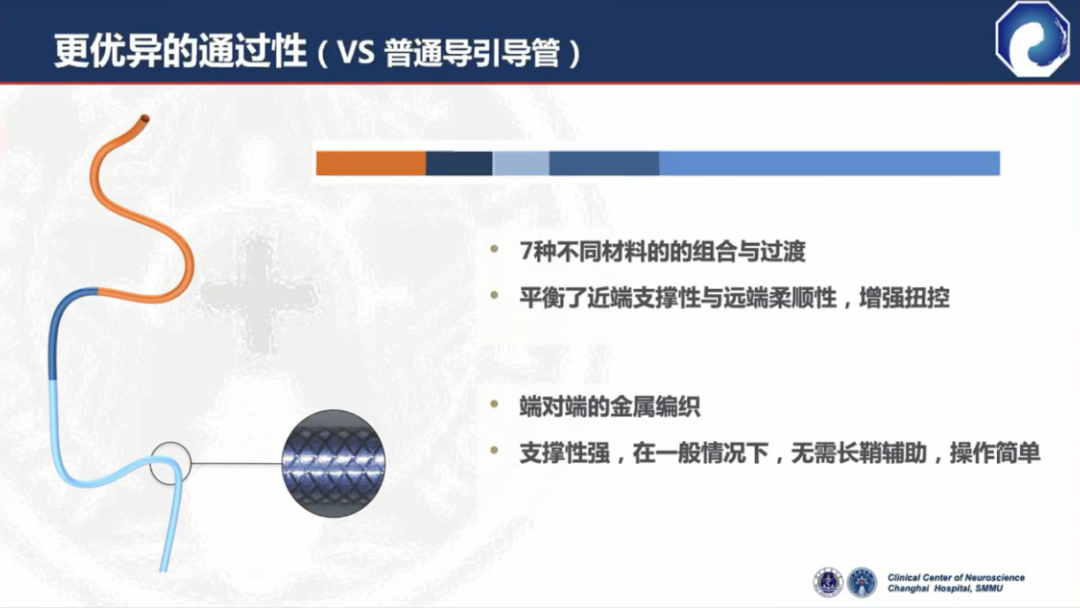

7种材料的组合带来了更优的通过性与近端支撑力

与竞品DA相比,弓部和近端支撑力更强

通桥医疗银蛇®DA设计特点